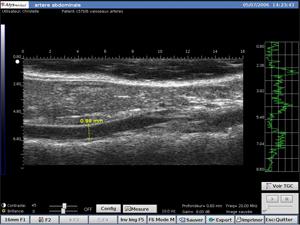

Arterial Vejiga

- Visualización en tiempo real e in vivo de estructuras anatómicas de pequeños animales

- Visualización y medición de la forma y el tamaño de los tumores subcutáneos y ortopédicos